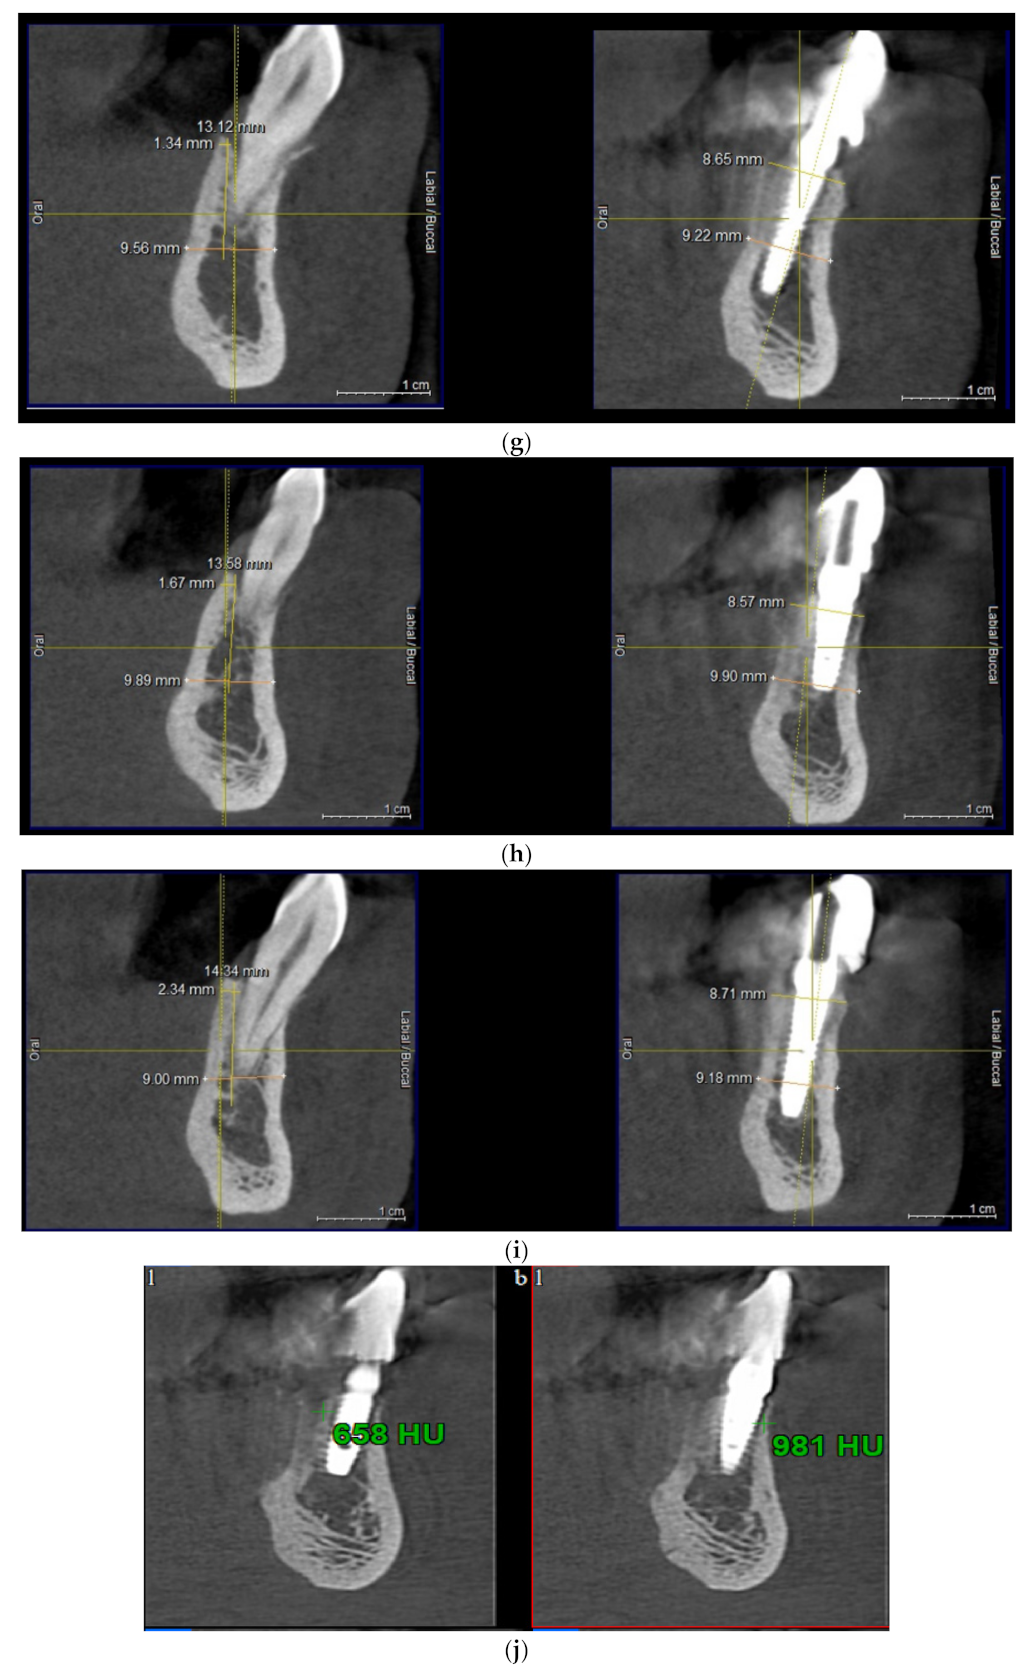

2.3. Evaluation of Clinical and Bone Parameters

3. Results